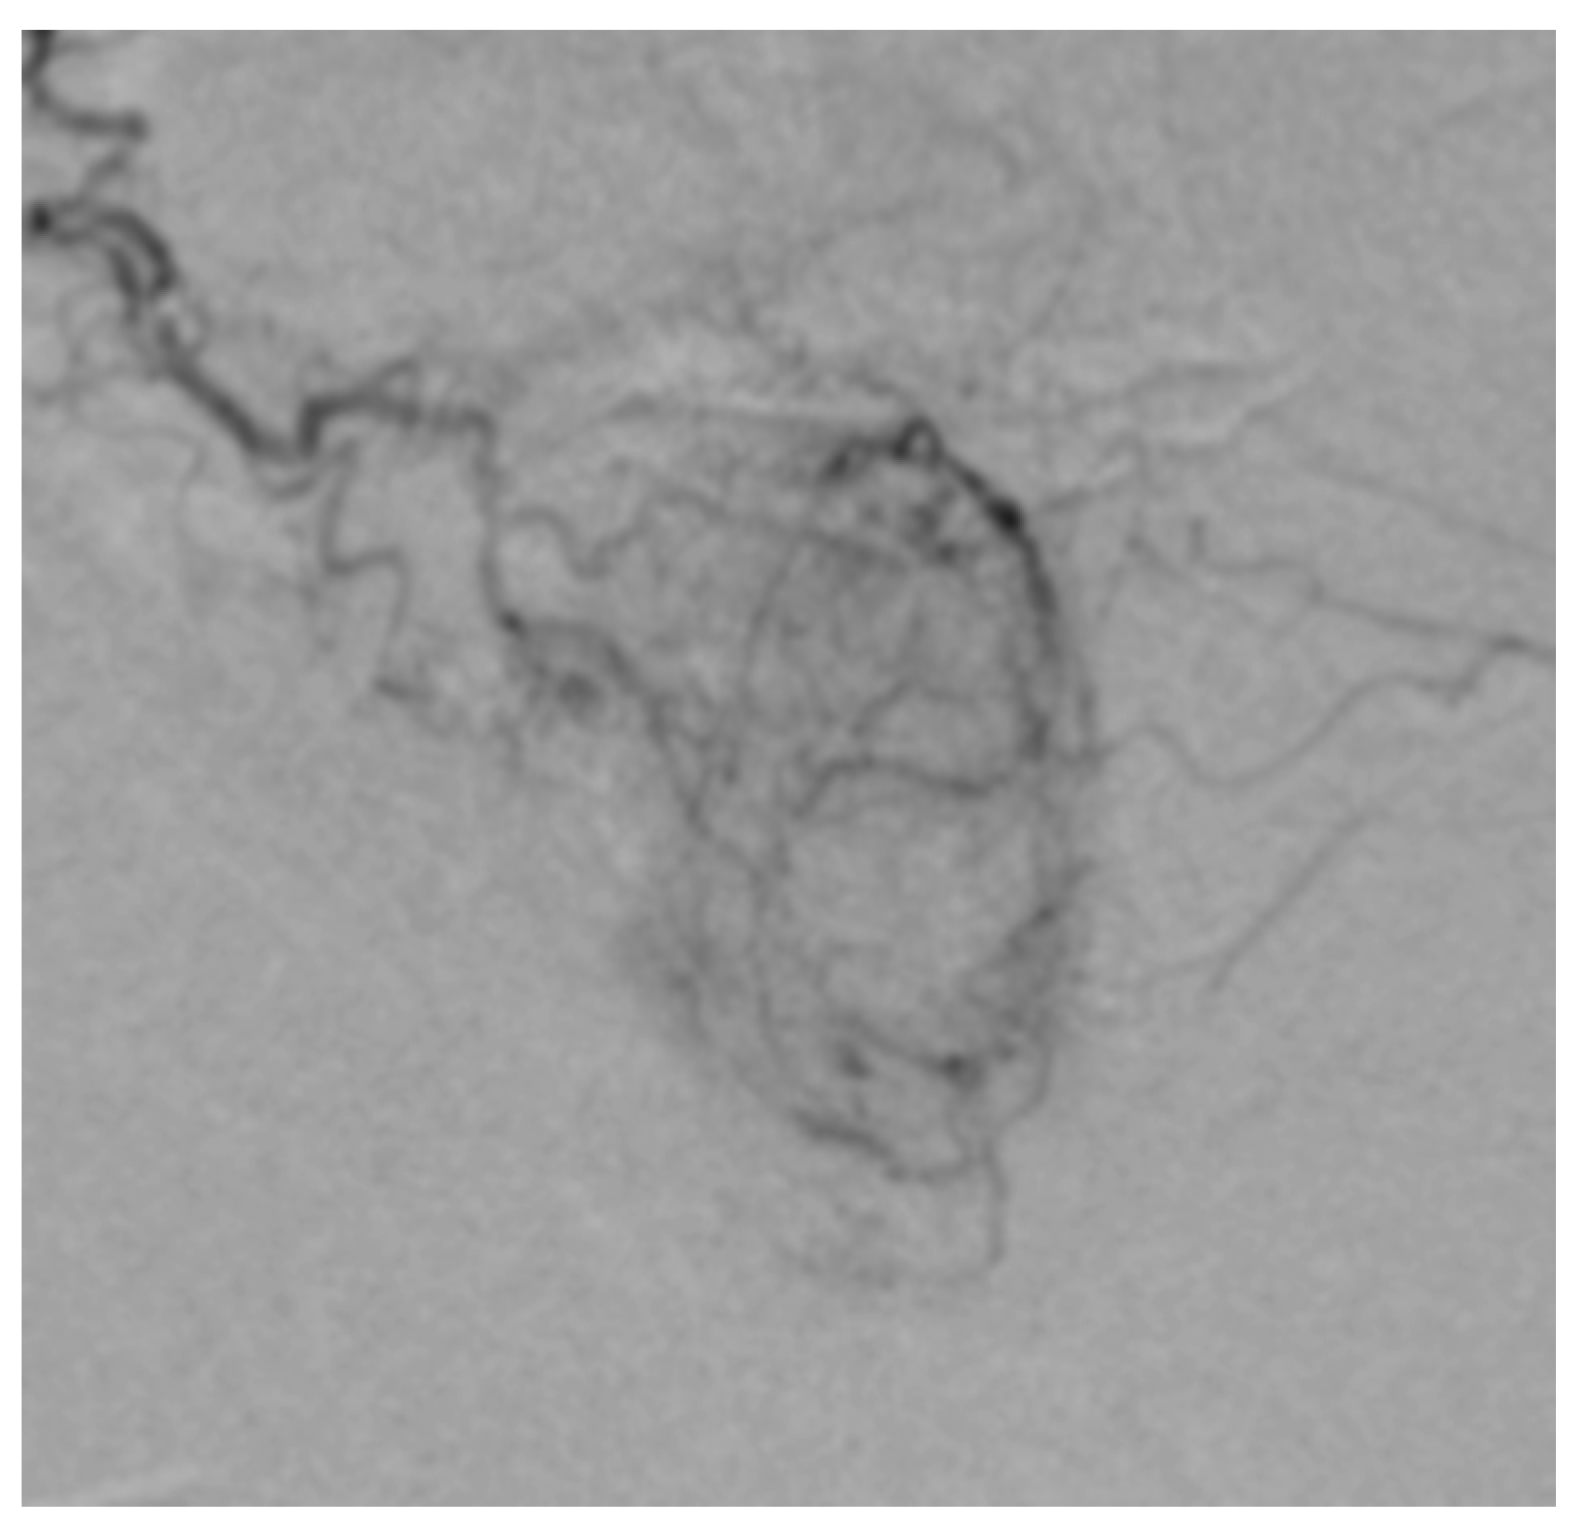

- Prostatic arteries realize the vascularization of the prostate, the anterior for the prostatic parenchyma and the posterior prostatic arteries for the prostatic capsule. Depending on the variability, we can frequently find a common trunk and a distal bifurcation near the prostate, but there are also cases of two PAs with different origins (Figure 1) [11].